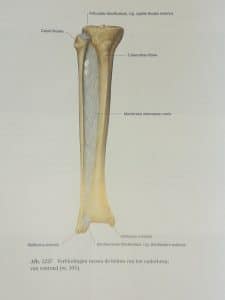

Mijn binnenste enkelknokkeltje (rechts op de foto – uiteinde van mijn scheenbeen) is met een schroef weer vastgezet aan mijn scheenbeen. Met een plaat en schroeven heeft de chirurg mijn kuitbeen proberen te repareren. En verder is er nog een lange horizontale schroef geplaatst om mijn kuitbeen aan mijn scheenbeen te fixeren. Dit is ter ondersteuning van het herstel van de zogenaamde syndesmose. Een syndesmose is een verbinding van beenderen door sterk bandweefsel (ligamenten). Deze banden maken dat er een sterke vork ontstaat waar de voet in opgesloten wordt en in kan scharnieren. Deze banden zijn niet in beeld te brengen op een röntgenfoto. Toch weten we dat de syndesmose beschadigd is omdat mijn voet zich tijdens de val heeft kunnen verplaatsen naar de buitenzijde van mijn onderbeen (zie figuur 2 en 3 in mijn verhaal van 28 december).